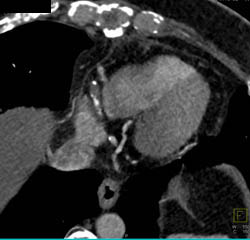

Stenosis in Aortic Arch and Origin of Great Vessels